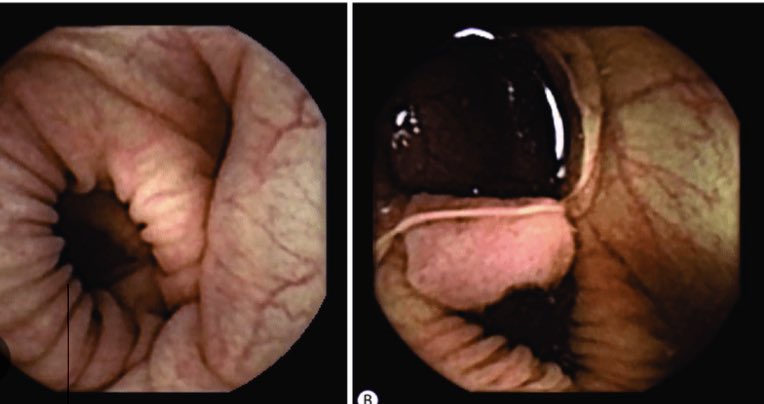

يتم إجراء التنظير الكبسولي عن طريق كبسولة تحوي كاميرا أو عدة كاميرات صغيرة، وبعد أخذ التحضير اللازم يتم بلع الكبسولة عن طريق الفم، مثل بلع حبة الدواء، دون الحاجة إلى التخدير.

تقوم الكبسولة بأخذ عشرات الآلاف من الصور خلال مرورها بالقناة الهضمية ، ويتجاوز عدد الصور ١٠٠ ألف صورة يتم تجميعها لخلق فديو تصل مدته ١٤ ساعة.

تستخدم كبسولة التنظير عادة في فحص الأمعاء الدقيقة والتي لا يمكن الوصول لها عن طريق منظار المعدة والقولون، وتشمل أمراض نزيف الجهاز الهضمي، وفقر الدم، ومرض كرون والأورام وغيرها.